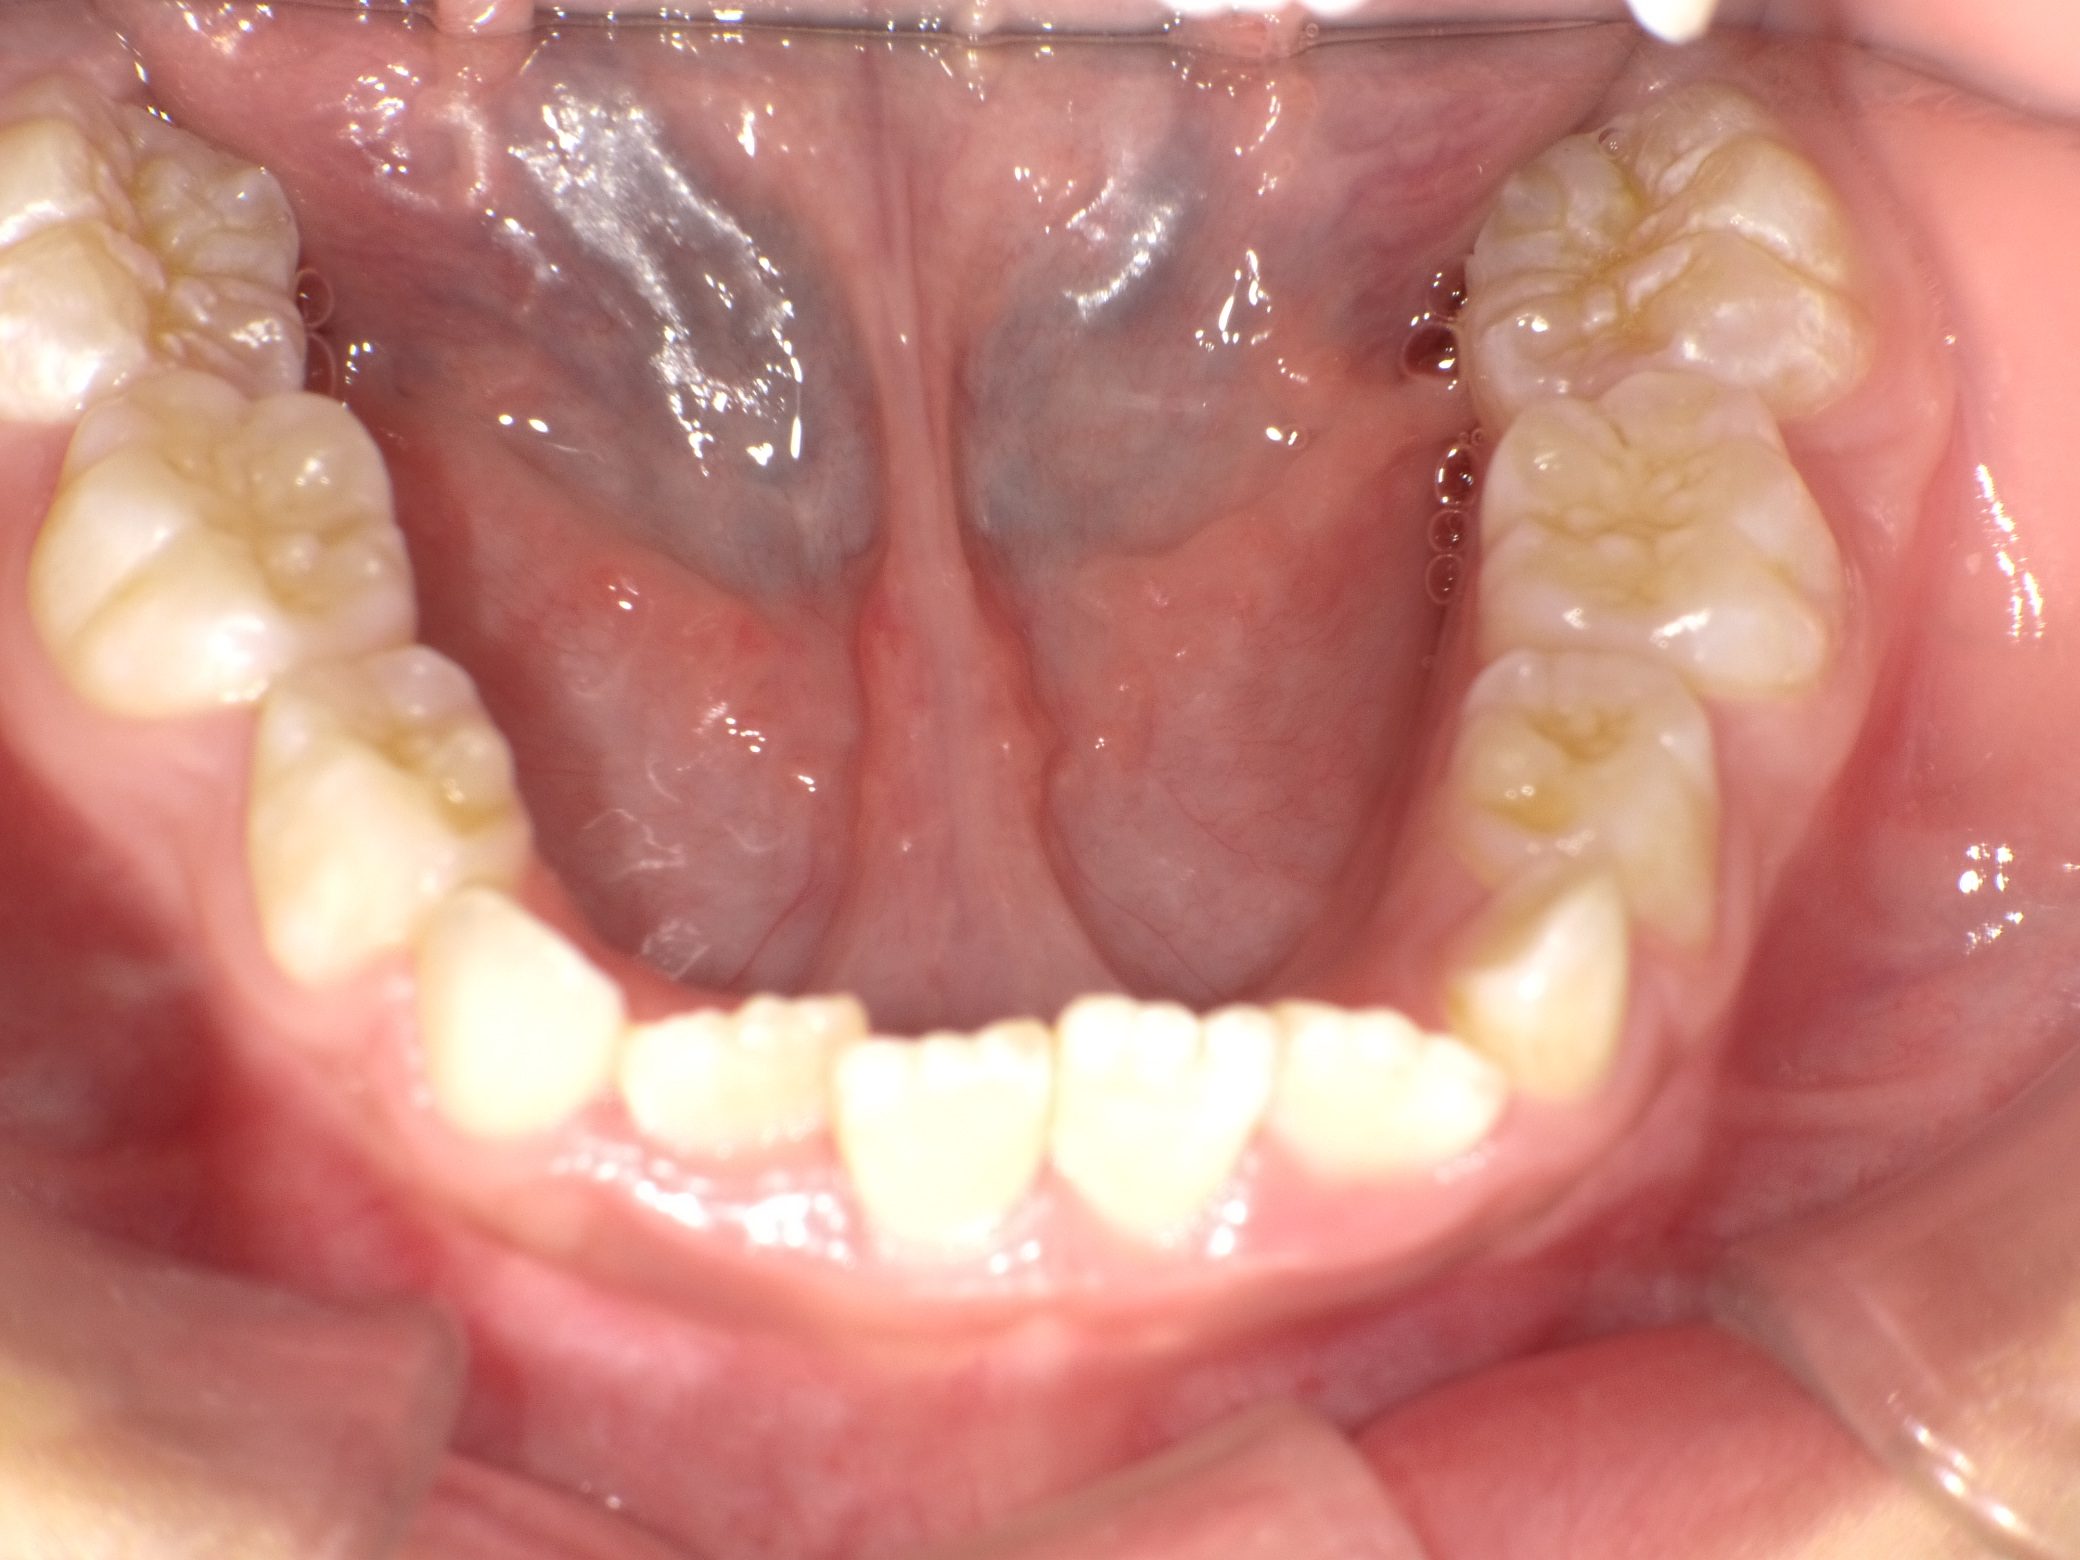

【小学生】マイオブレース矯正 受け口を改善 ④

小学生で開始

マイオブレース

受け口

非抜歯

1期治療のみで改善

Before

After

治療期間

2年

治療開始

8歳

種類

マイオブレース矯正

使用装置

機能矯正装置

コメント

機能矯正装置を利用

しっかり取り組んでくれたので 治療後3年 後戻りはありません